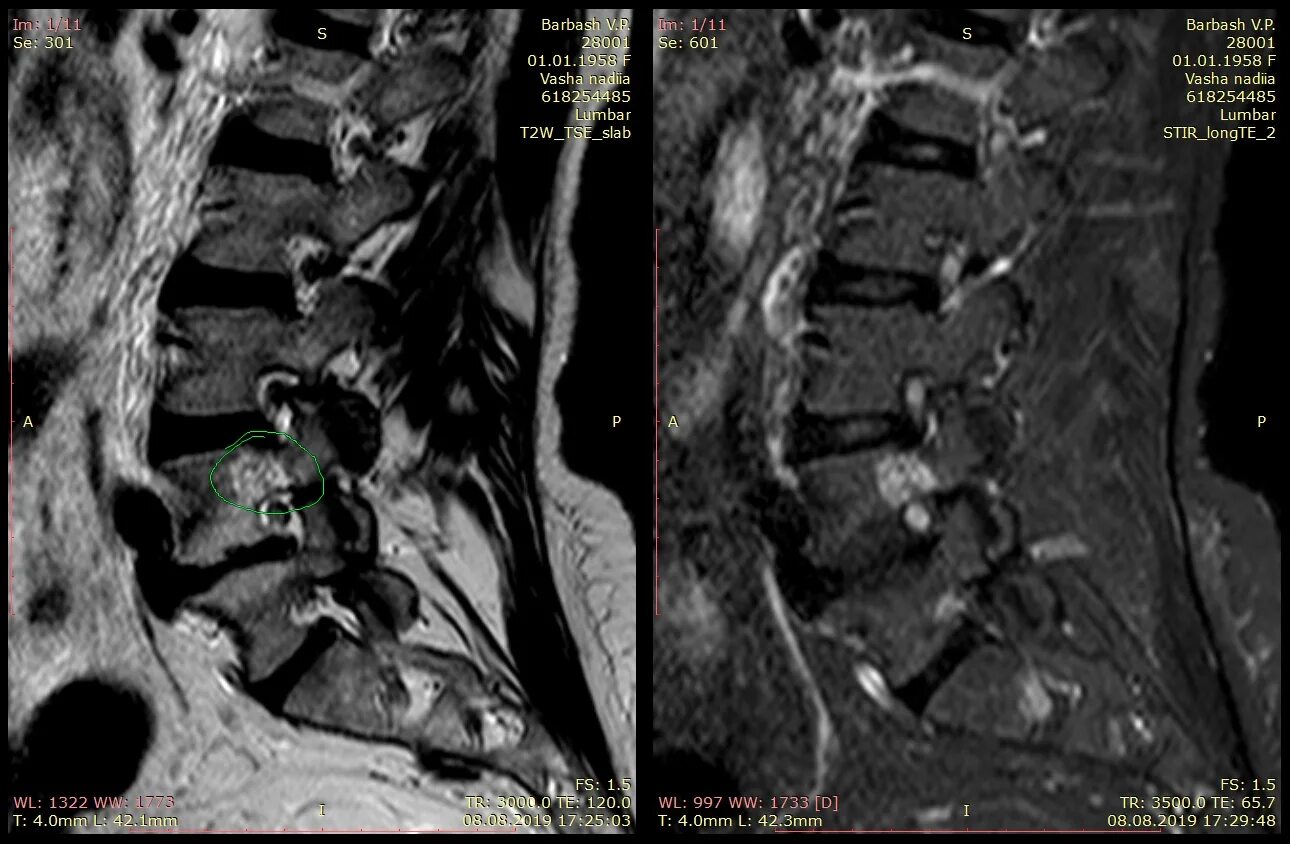

Спондилодисцит мкб